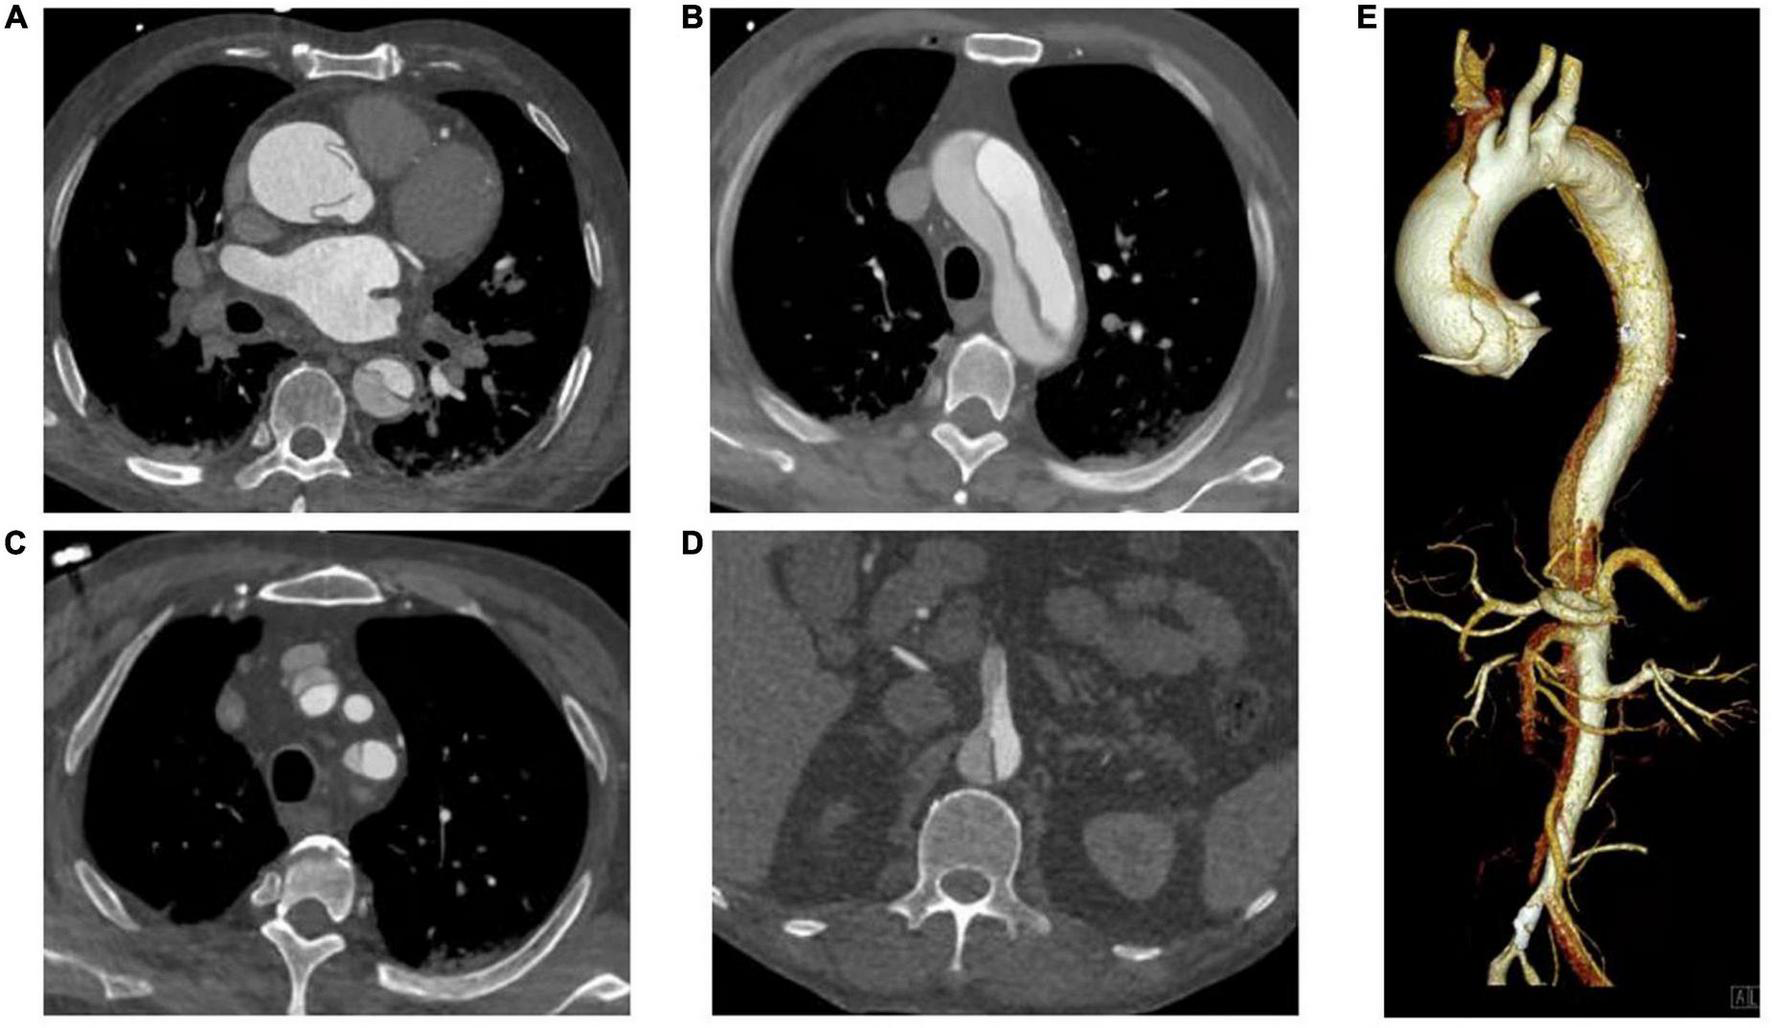

In recent decades, ATAAD has generally been defined as any disease involving the ascending aorta within 14 days after the onset of symptoms (4). Since the time delay from symptom onset to surgical treatment in ATAAD patients significantly changes the survival rate (7), this study selected patients within 7 days of symptom onset according to the new aortic dissection time classification proposed by the IRAD (13). The inclusion criteria were patients aged 18–80 years, diagnosed with ATAAD (CT angiography of the Aorta, Figure 1) and undergoing total aortic arch replacement. The primary exclusion criteria were conservative treatment, death before or during surgery, and symptom onset > 7 days.

FIGURE 1

CT Angiography of the Aorta. (A) Ascending aorta; (B) Aortic arch; (C) Branch of aortic arch (involving brachiocephalic trunk and left subclavian artery); (D) Aortic dissection involving superior mesenteric artery; (E) Volumetric CT scanning: 3D reconstruction.